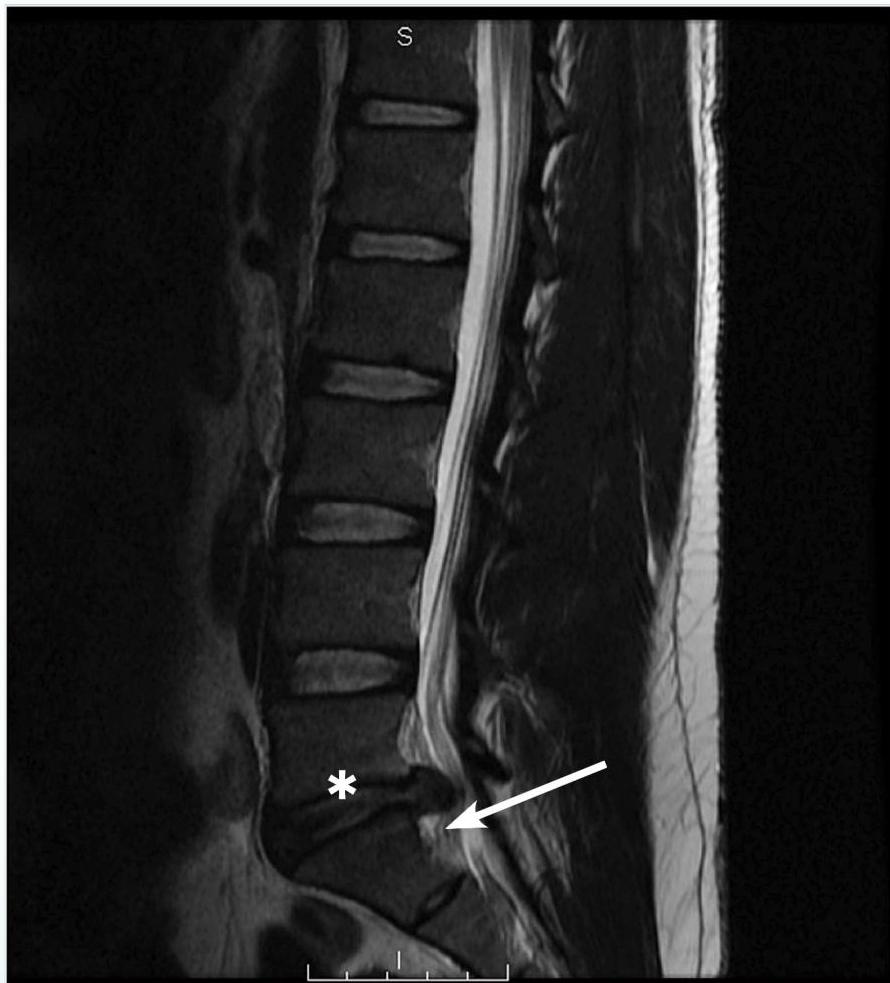

Figure 4. Posterior Disc Herniation

Magnetic resonance imaging (MRI) T2 sagittal images without contrast demonstrates a L5-S1 posterior disc herniation in a patient with back pain and sciatica symptoms. Since his symptoms had been ongoing for 3 months, were resistant to medical therapy, and had concordant MRI findings, he underwent epidural steroid injection treatment. The asterisk is over the L5 vertebral body; the arrow points to the herniated disc.

Image courtesy of Pierre Borczuk, MD.